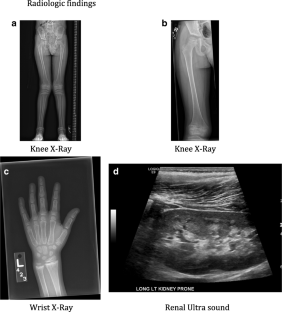

Fig. 1